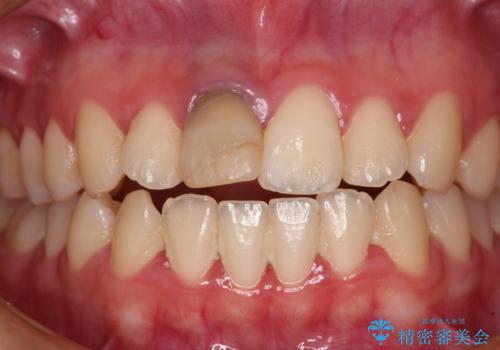

- 虫歯により神経を取り除いた前歯の変色が気になるとのことで来院された患者様です。

レントゲン写真より、歯根の炎症が認められなかったため、ファイバーコアによる土台築製後、オーダーメイドタイプのオールセラミッククラウンにて補綴することとしました。